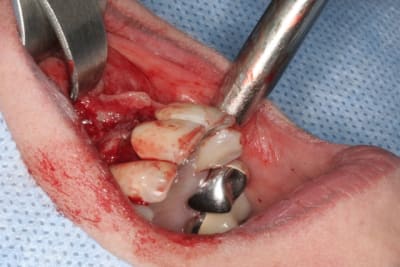

tien, ce matin, extraction de 24/25, curetage méticuleux, forage, comblement du gap, pose des 2 implants qui se sont bloqués à 50Ncm au CA sur les 3 ou 4 mm apicaux, pose des vis de cicat, sutures...35min....tranquille...

un autre cas EII MCI sur 11/21...mais en photos (j'ai aussi la vidéo, faut que je la passe sur youtube)